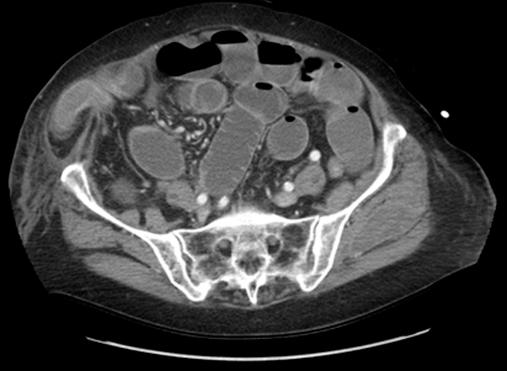

A Spigelian hernia is a rare type of hernia that occurs through a defect in the anterior abdominal wall adjacent to the linea semilunaris. Estimation of its incidence has been reported as 0.12% of all abdominal wall hernias. Traditionally, the method of repair has been an open approach. Herein, we discuss a series of laparoscopic repairs.

Three patients are presented. All were evaluated and taken to surgery initially for a different disease process, and all were incidentally found to have a spigelian hernia. These patients underwent laparoscopic repair of their hernias; 2 were repaired intraperitoneally and one was repaired totally extraperitoneally. Two patients initially underwent a mesh repair, while the third had an attempted primary repair.

There is evidence that supports the use of laparoscopy for both diagnosis and repair of spigelian hernias. There are also reports of successful repairs both primarily and with mesh. In our experience with the preceding 3 patients, we found that laparoscopic repair of incidentally discovered spigelian hernias is a viable option, and we also found that implantation of mesh, when possible, resulted in satisfactory results and no recurrence.